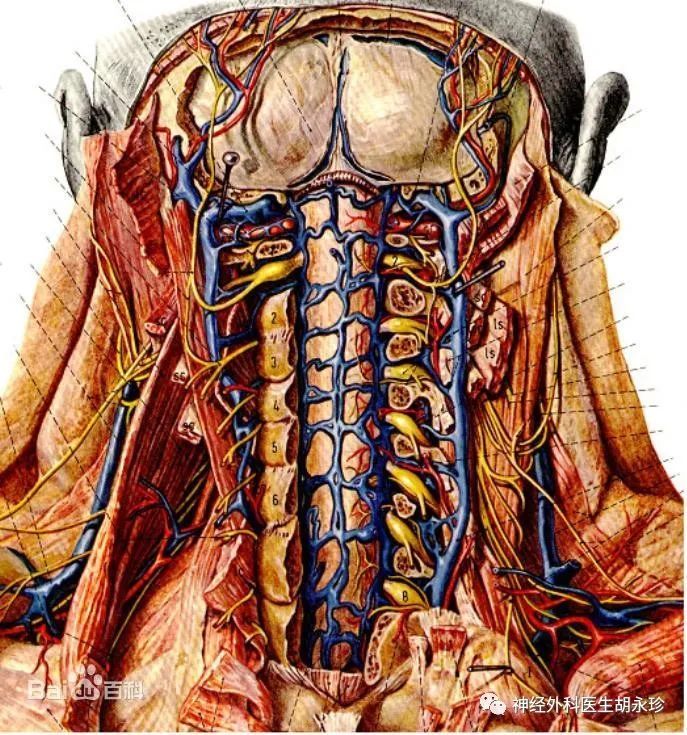

颈2神经根及其周围静脉丛的解剖关系 腾讯新闻